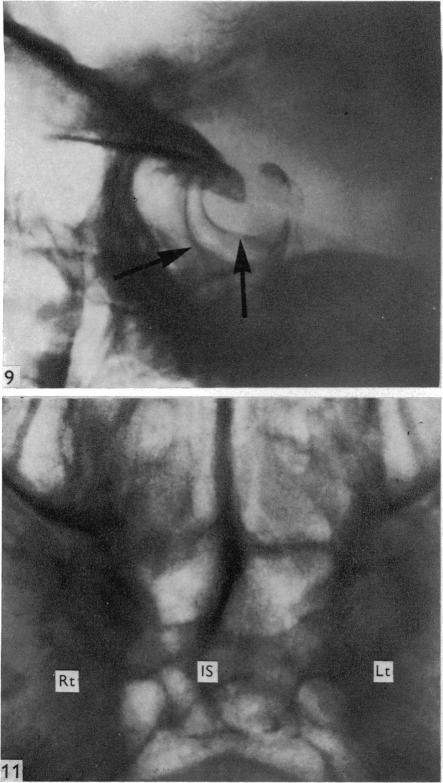

Surgical aspects of the anatomy of the sphenoidal sinuses and the sella turcica.

J Anat. 1977 Dec;124(Pt 3):541-53.